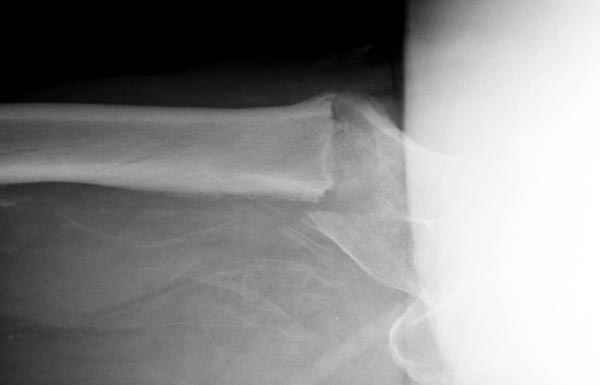

Изначально была выбрана не правильная точка введения стержня, в связи с чем в конце, я подчеркну, в конце операции произошло из-за напряжения между прокимальным концом канала бедра и стержнем разрушение в/3 бедра.

Проволока наложена потому, что при введении штифта не прошли эту зону римером и произошли сколы на концах отломков.

Под ЭОП во время операции такого смещения не было. Мы бы конечно не отпустили этого больного с такой картиной (сами бы что-то сделали или к вам отпр).

В общем, сделали. См. приложение.

Длина и из-за этого ось получились не совсем такие, как хотелось бы, все-таки срок после той операции уже 6 недель. Может быть, стоило провести дистракцию аппаратом неделю-другую. Заранее спасибо за комментарии и критику.